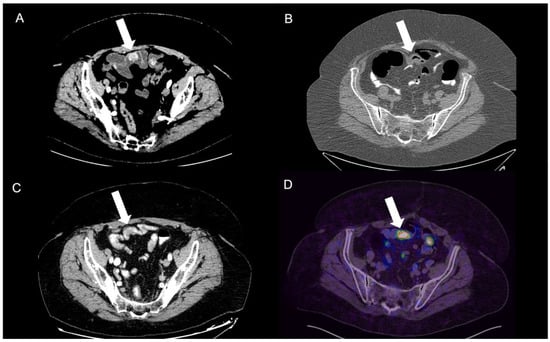

2.2.2. Positron Emission Tomography (PET)